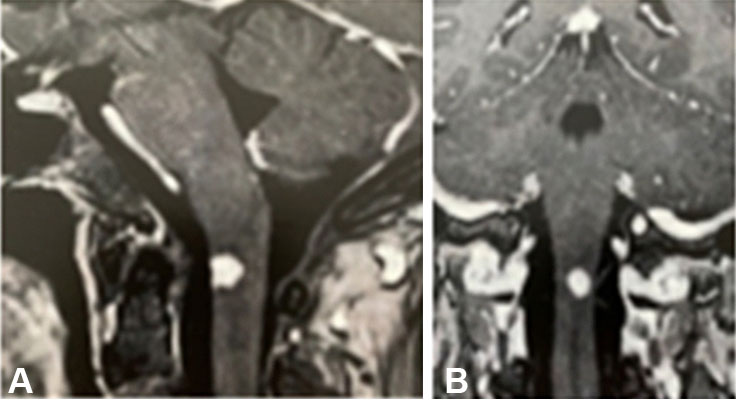

In January 2017, the patient had seizures despite the use of anticonvulsant drugs, and the doses of these medications were increased. She remained stable until May 2017, when she felt dizzy, experienced loss of balance, and had headaches. She underwent skull MRI that showed an area of cerebral ischemia of non-specific cause and slight dilation of the ventricular system (Figure 4).

Figure 4: Magnetic resonance imaging showing an area of cerebral ischemia of non-specific cause and slight dilation of the ventricular system.

Share Image: